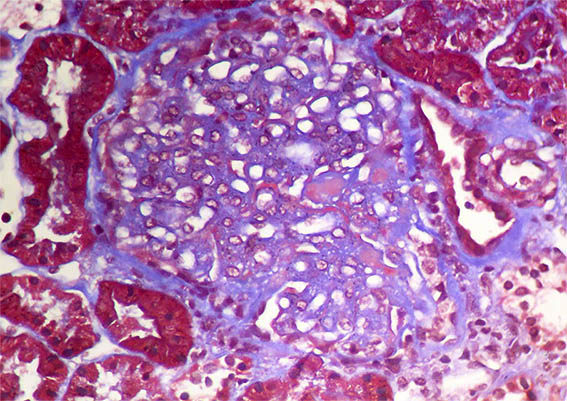

Figure 4. Masson's trichrome stain, X400.